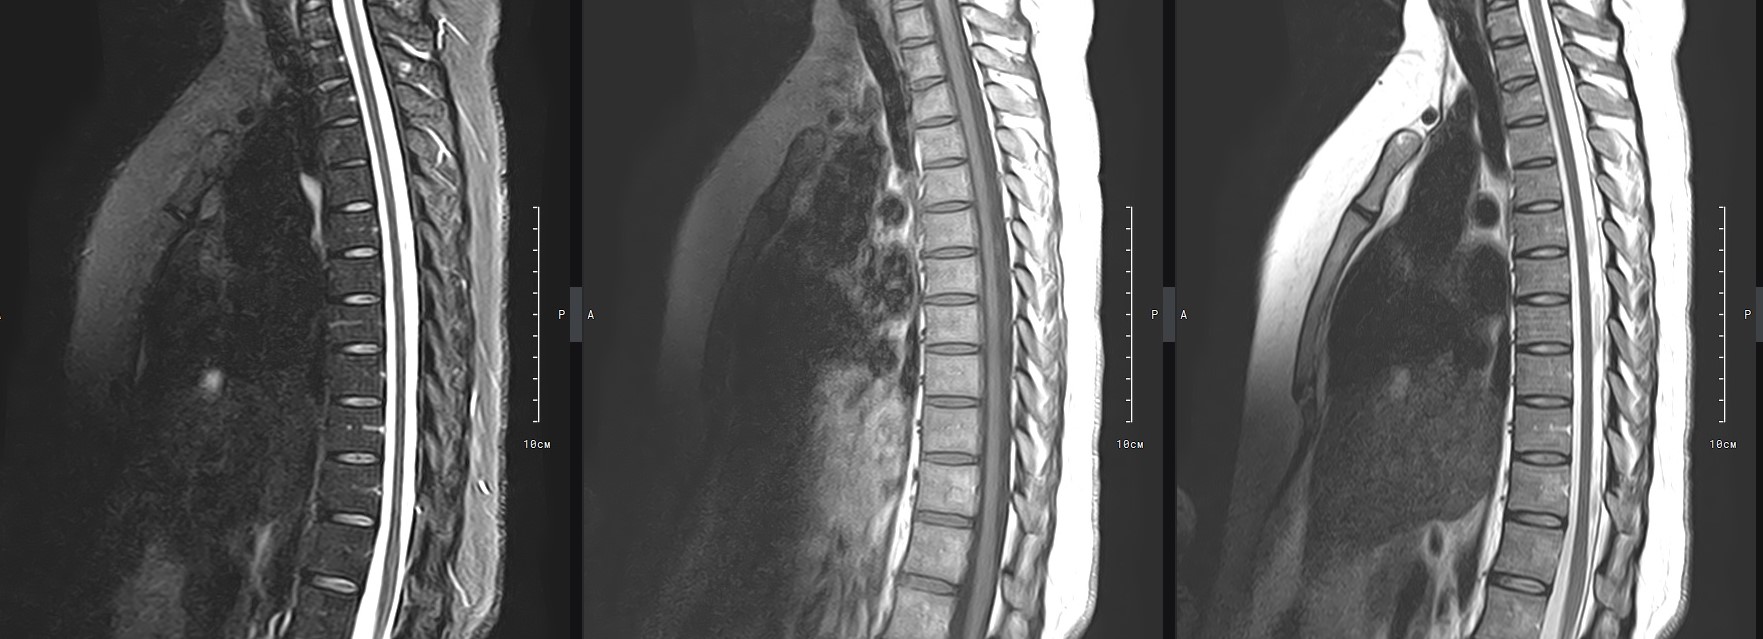

МРТ является современным высокоточным исследованием грудного отдела позвоночника, с помощью которого можно диагностировать различные заболевания, в том числе воспалительные, дегенеративные и опухолевые процессы. Преимуществом данного метода является его безопасность (отсутствие рентгеновского излучения), безболезненность, неинвазивность, при этом высокая информативность.

Клиника «Доступная медицина» оснащена новейшим томографом экспертного класса TOSHIBA VANTAGE TITAN 1,5 Тесла, который позволяет получать превосходные изображения с мельчайшей детализацией всех структур исследуемой области. Это позволяет ставить точный диагноз и выявлять различные заболевания позвоночника на самой ранней стадии.

В большинстве случаев проводится стандартная магнитно-резонансная томография грудного отдела позвоночника без использования контраста, однако в некоторых случаях требуется контрастное усиление, например, для диагностики опухолей малых размеров. Для этого применяется безопасное контрастное вещество на основе гадолиния (элемент, относящийся к редкоземельным металлам), которое полностью выводится из организма в течение суток преимущественно почками.

С помощью МРТ грудного отдела выявляют следующие заболевания позвоночника:

• новообразования;

• степень повреждения спинного мозга в случае переломов тел позвонков;

• грыжи Шморля;

• травматические повреждения тел позвонков и остистых отростков (трещины, переломы, смещения и пр.) — при недоступности КТ;

• разрывы, растяжения связок;

• травмы спинного мозга, нервных корешков;

• протрузии;

• грыжи межпозвонковых дисков;

• остеохондроз позвоночника;

• стеноз спинномозгового канала;

• сосудистые патологии;

• остеомиелит, спондилодисцит;

• рассеянный склероз;

• спондилоартроз;

• спондилез.